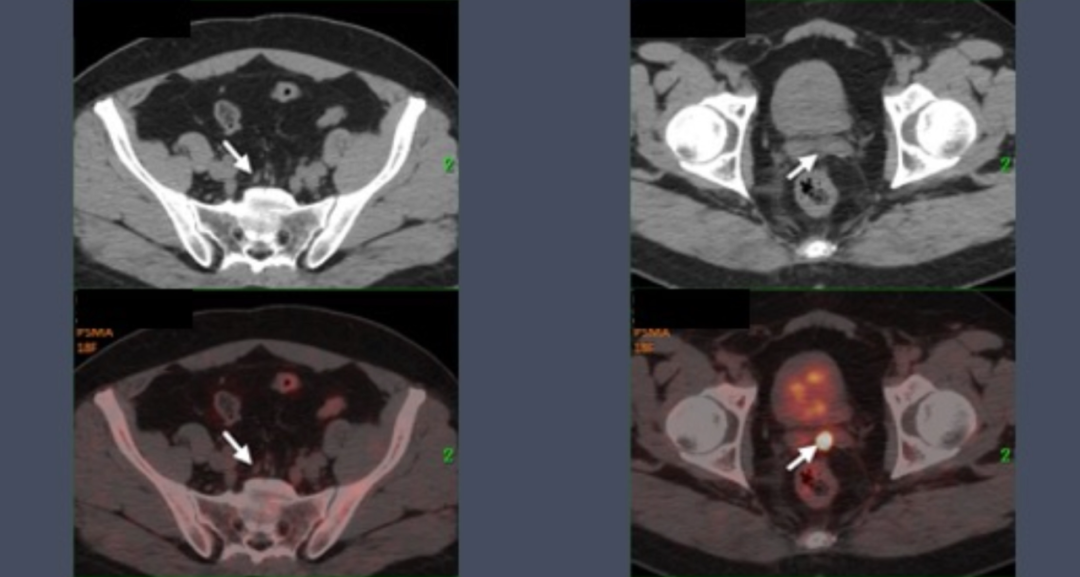

患者为43岁中年男性,初诊PSA 54 ng/mL,穿刺病理为前列腺腺泡腺癌(Gleason 5+5)。MRI显示侵犯精囊、直肠,盆腔及腹膜后多发淋巴结转移。PSMA PET/CT显示前列腺弥漫性PSMA高表达,骶前、腹膜后及两侧髂血管淋巴结转移,双侧髂骨局灶性PSMA高表达。

在3周期PSMA核素治疗后,患者复查PSMA PET/CT提示:前列腺右侧外周带局灶PSMA表达略增高,左侧精囊腺局灶性PSMA高表达相仿。髓前、腹膜后及双侧骼血管淋巴结退缩,髂骨未见PSMA表达增高,考虑活性受抑。

叶定伟教授表示:“我们与Peter Mac癌症中心方案的主要区别在于,在PSMA核素治疗的基础上联合了新型内分泌治疗,患者采用这种联合治疗后的影像学退缩非常明显,PET/CT显示治疗后前列腺病灶活性显著降低、骨病灶活性受抑、淋巴结退缩;PSA由初诊的53.7 ng/mL降低至术后0.01 ng/mL;病理检测进一步证实了这种治疗方案显著效果——仅有1%的瘤荷残存并且切缘阴性。”